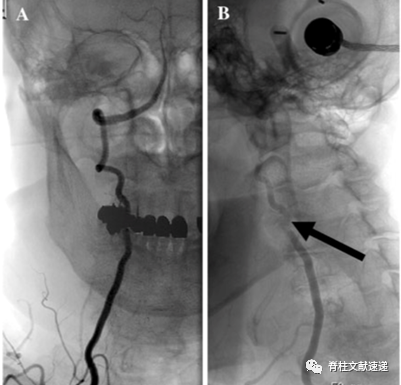

5) DSA是BHS诊断的金标准。头位中立位和侧转头时血管情况、具体受压部位以及侧支循环情况。

图注:上图为椎动脉DSA,图A为头在中立位时的C1/2处左侧的椎动脉,无异常;图B为头向右旋转40度时,V3段椎动脉完全闭塞了。

图注:上图为椎动脉DSA,图A为头在中立位时右侧的椎动脉,无异常;图B为头部右转时,V2段(C3/4处)椎动脉血流明显减少。